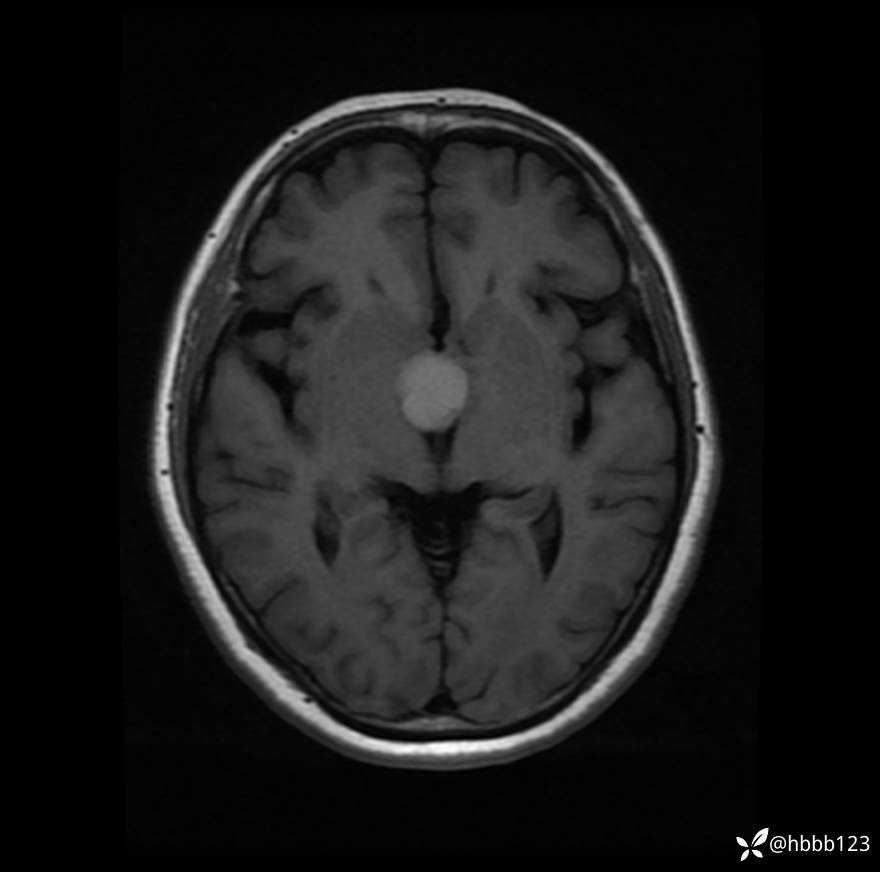

T1WI: